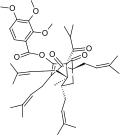

- Natural and semi-synthetic analogues of Hyperforin

-

-

Aristoforin

Aristoforin -

Hyperforin trimethoxybenzoate

Hyperforin trimethoxybenzoate -

Tetrahydrohyperforin

Tetrahydrohyperforin -

Hyperforin nicotinate

Hyperforin nicotinate